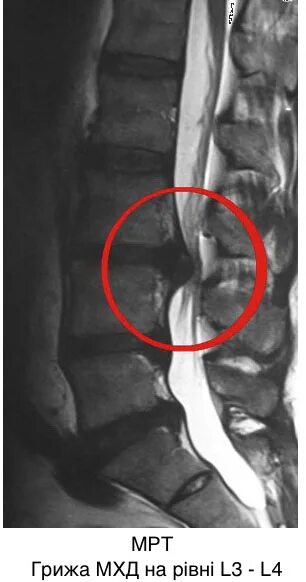

Грыжа диска мрт